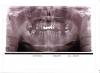

attachicon.gif01.JPGПомогите принять решение. За счёт неправильного прикуса сформировались замки которые увеличили нагрузку на зубную поверхность и зубы стираются. Врач предлагает депульпировать все зубы и постепенно меняя коронки исправить прикус и затем окончательно протезировать. Жалоб у пациента в данный  момент нет. Причина обращаемости хотели заново пролечить каналы ,так как каналы плохо пройдены, и запломбированы эндометазоном, и хотелось сделать реставрацию резцов , так как зубы стёрлись и даже при при смыкании не достают друг друга. Пациенту 53 года. Можноли просто сделать реставрацию зубов и протезировать нижние зубы , а свеху имплантировать два зуба и всё. Врач говорит что реставрация разобьётся за месяц ,а импланты просто не сядут как надо.  Хотелось бы ёщё мнений Всё же уже возраст, и сумма так скажем не малая.